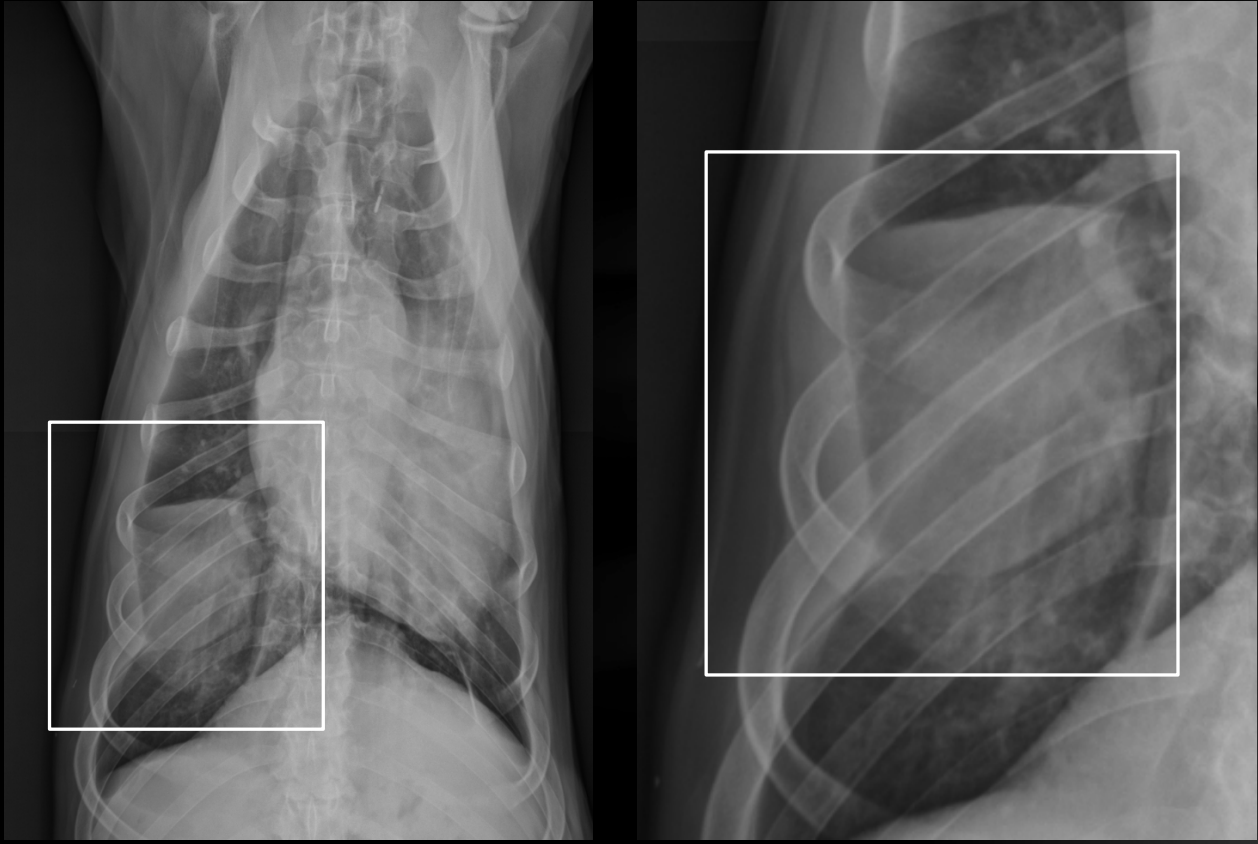

What is the chronicity of these rib fractures?

Left: acute

-displacement

-sharp margins

Right: chronic

-callus formation